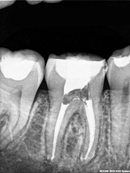

Root Canal Cases